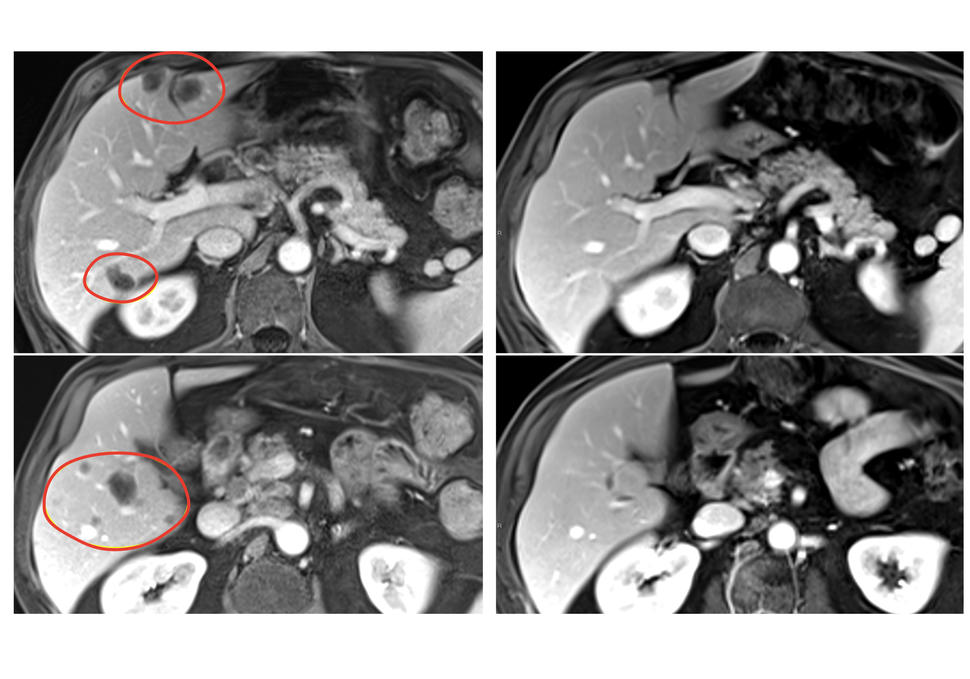

Ten months after treatment with selected TIL therapy and pembrolizumab, a patient with rectal cancer had substantial shrinkage of multiple liver metastases (left scans, circled in red).

Credit: Center for Cancer Research/National Cancer Institute